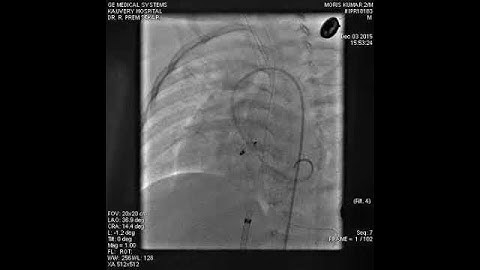

LV Angiogram profiling Perimembranous VSD prior to closure with a symmetrical PMVSDO